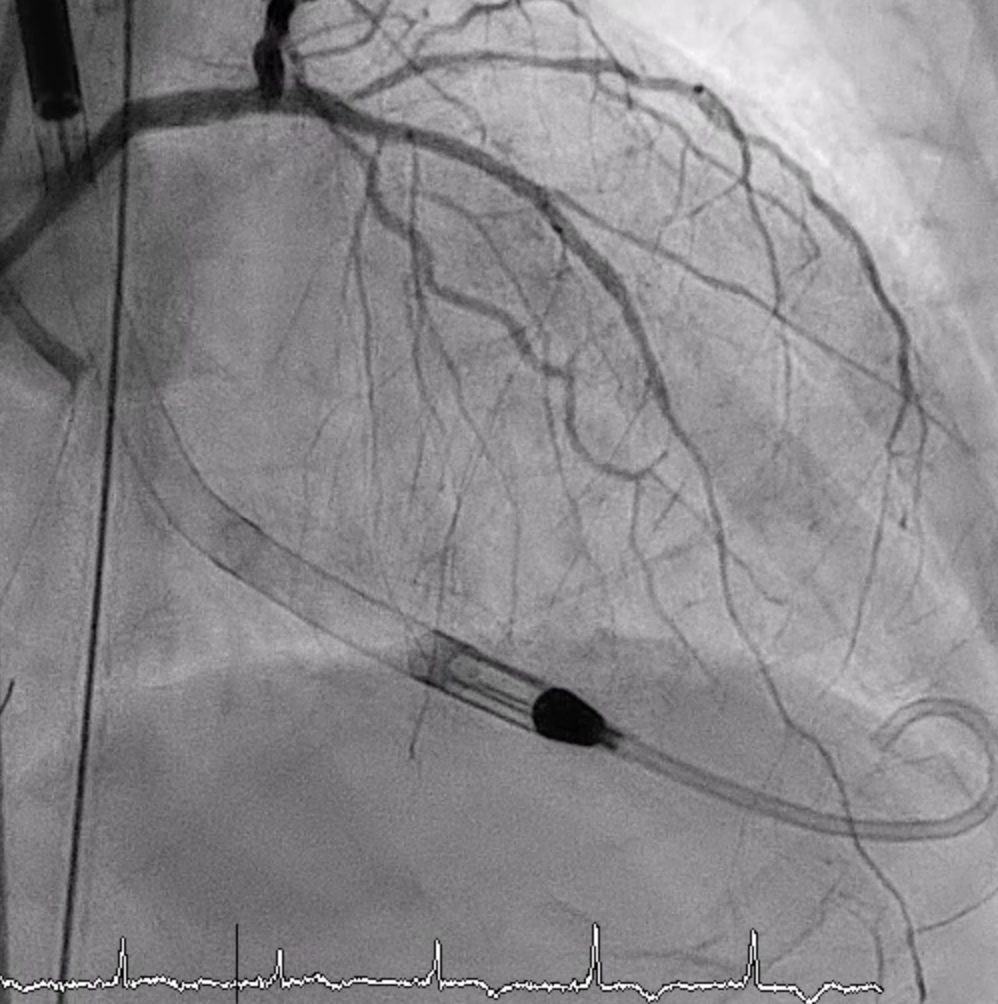

LMCA was engaged with an EBU 3.5. Several wires failed to cross the p-LAD CTO, but Gaia 1st entered the true lumen and advanced to DB2 via Finecross. Small-balloon predilation (1.2–2.0 mm) was done. IVUS confirmed true lumen and MLA 2.43 mm©÷ at the CTO entry. A double-catheter Sasuke technique enabled CTO crossing. A 2.0¡¿38 mm X-Skypoint stent was deployed, followed by POT and high-pressure post-dilation, achieving TIMI 3 flow.LCX Intervention: